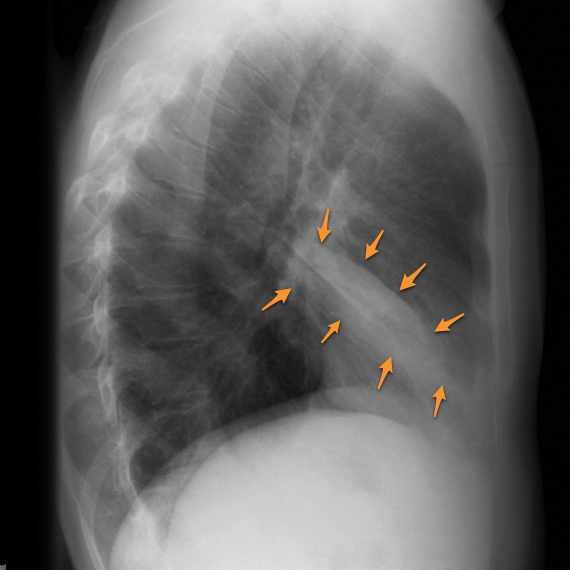

Round Atelectasis

Focal atelectasis with a round morphology that is always associated with an adjacent pleural abnormality (e.g. pleural effusion, pleural thickening or plaque, pleural neoplasm, etc). Round atelectasis is most common in the posterior lower lobes. All five of the following findings must be resent to diagnose round atelectasis: 1. Adjacent pleura must be abnormal. 2. Opacity must be peripheral and in contact with the pleura. 3. Opacity must be round or elliptical. 4. Volume loss must be present in the affected lobe. 5. Pulmonary vessels and bronchi leading into the opacity must be curved, this is the comet tail sign.